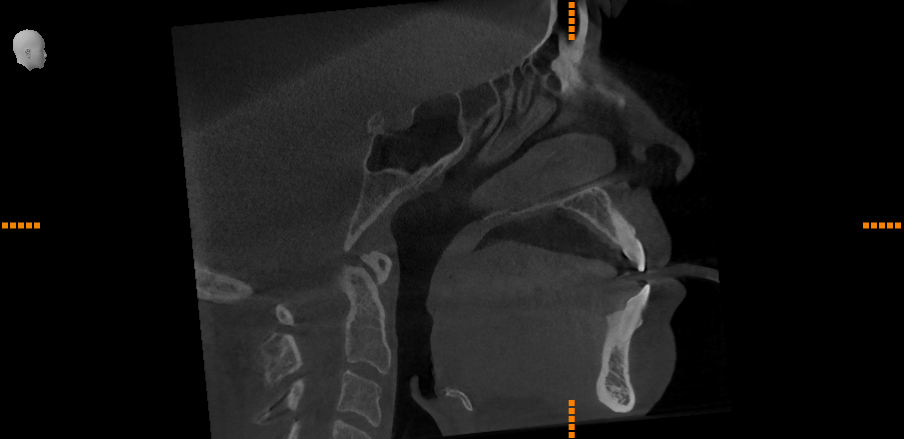

CBCT

A CBCT scan or cone-beam computed tomography scan can be beneficial in obtaining a better overall view of your entire mouth, jaw, nasal, sinus and throat areas. The Dentsply Sirona Axeos CBCT creates fantastic 3D images that show bone, airway, and soft tissue in these areas, as well as any dental work you may have.

CBCT scanners use a cone-shaped X-ray beam and capture images in a single rotation, resulting in a lower radiation dose compared to traditional CT scans. This makes CBCT a safer option for patients, while still providing valuable diagnostic information.